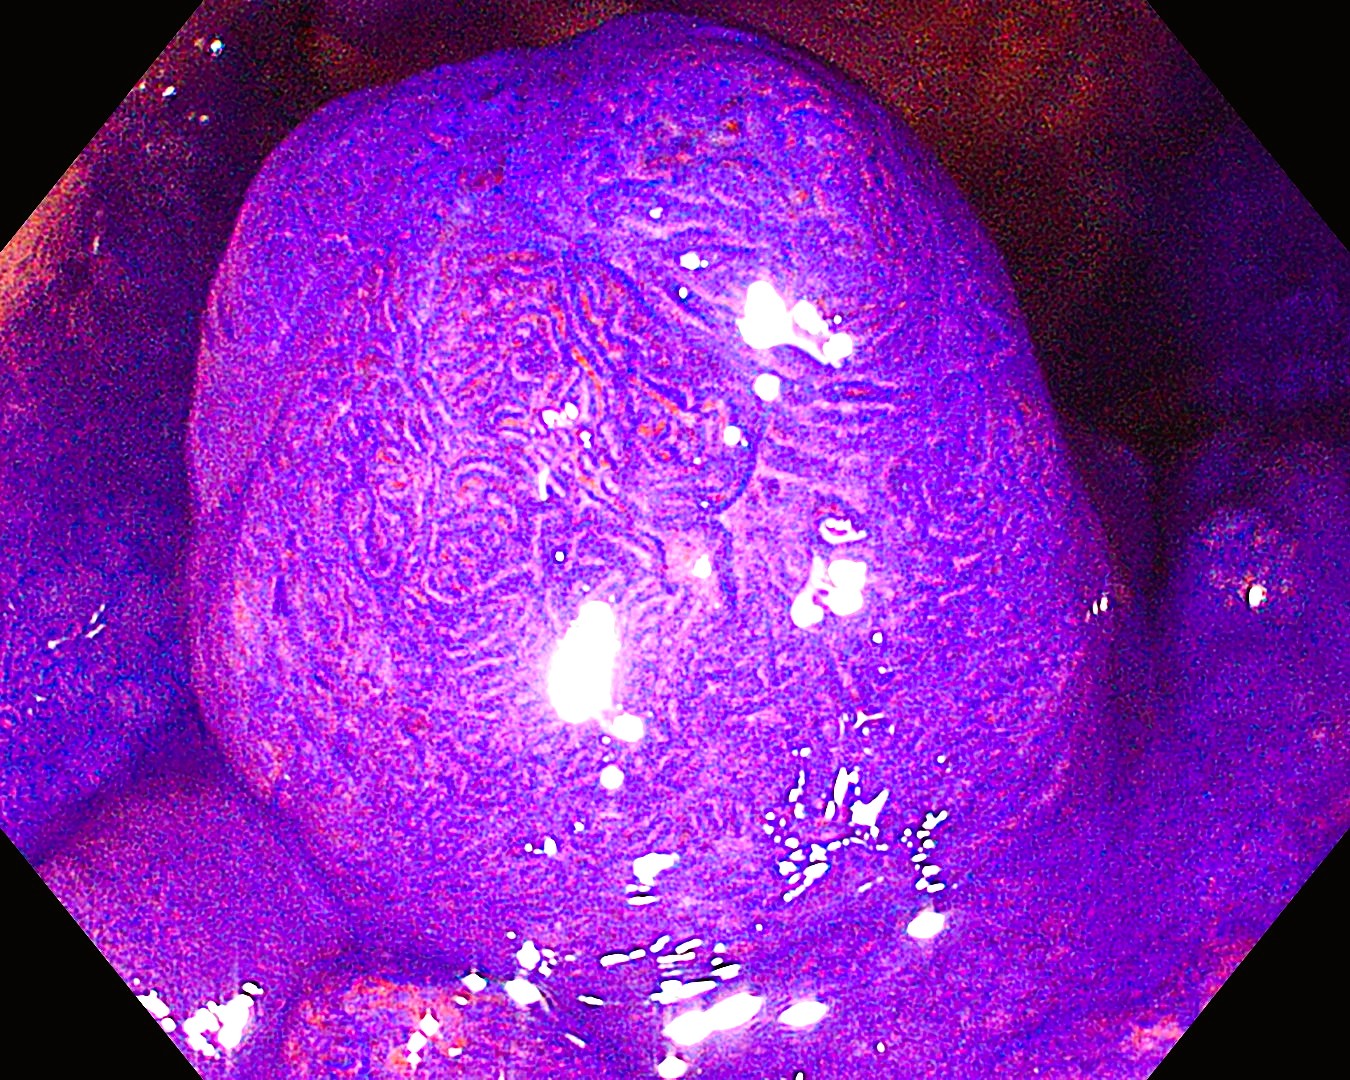

• NBI+TXI観察①(拡大)

切替前:NBI強調設定:B8

NBI+TXIレベル:高

図6

NBI+TXI観察では、従来のNBIに比べ、表面構造・血管走行ともに強調される。不明瞭な関心領域内に、分岐の異常な表面構造や分布の不均一な血管走行が確認され、JNET type 2B と診断しえた。